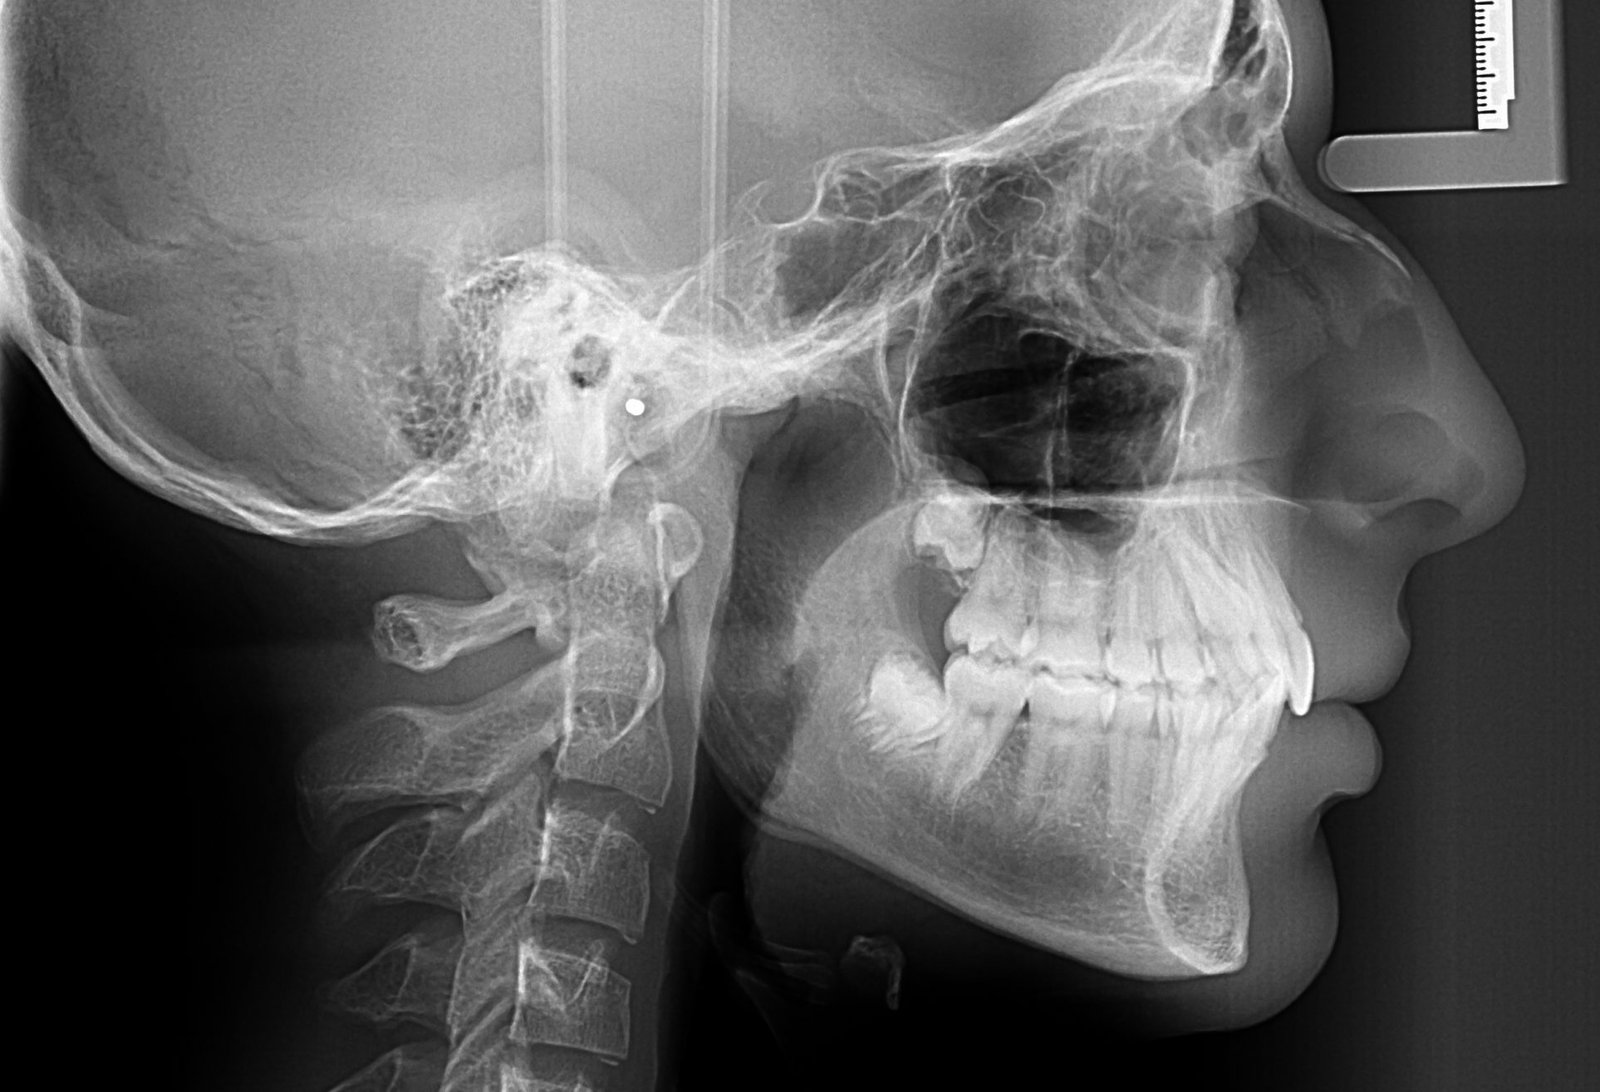

Teleradiografia de profil

Teleradiografia de profil este recomandată în cazurile în care se planifică utilizarea unui aparat ortodontic pentru alinierea dinților sau pentru ajustarea structurii osoase și a ocluziei pacientului. Aceasta oferă o imagine clară a relației dintre dinți, maxilare și oasele craniului, permițând medicului ortodont să efectueze măsurători precise pentru stabilirea diagnosticului și elaborarea unui plan de tratament personalizat.